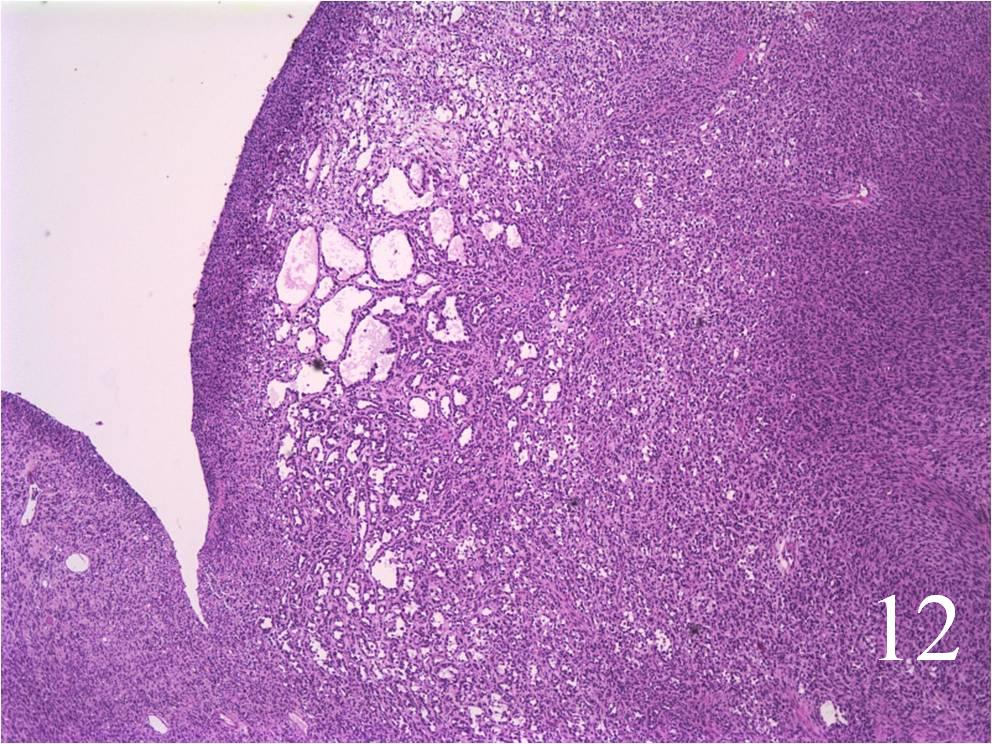

Microscopic

- Embryonal:

- Small round blue cells (Fig. 12-15)

- Round, oval, polygonal cells

- Fibrotic/myxoid stroma

- Rhabdomyoblast: well differentiated will have cross striations

- Alveolar:

- Tumor cells grow in nest or clusters

- Identify rhabdomyoblasts with cross striations